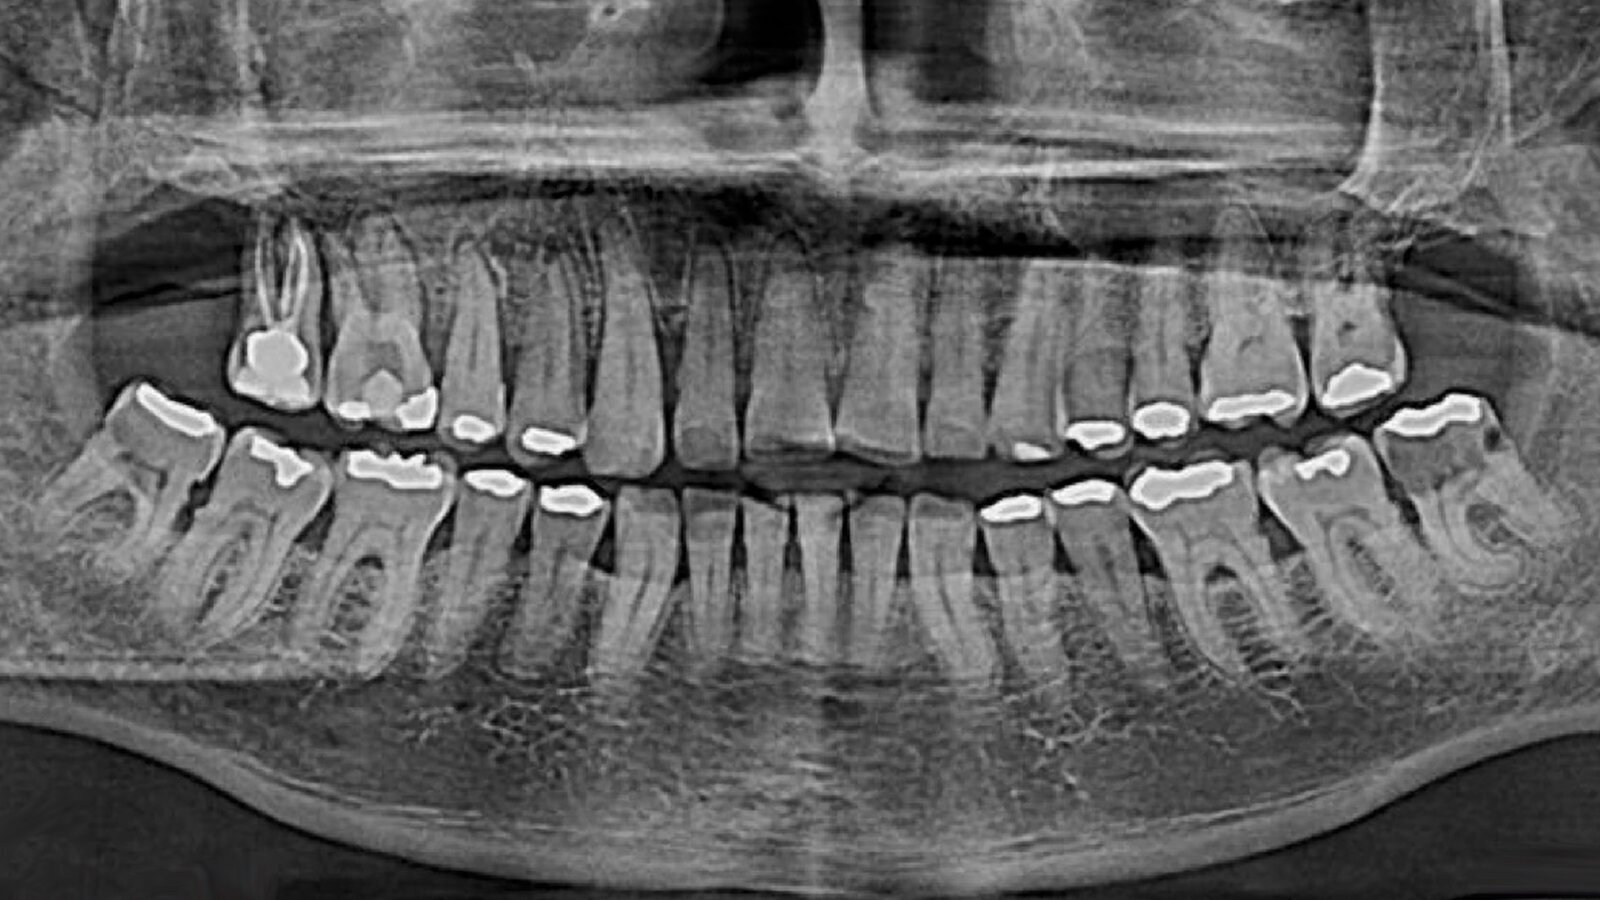

Figura 1. Imágenes radiográficas iniciales en las que se observa la pérdida ósea horizontal y vertical respecto al diente 18, lo que conlleva a que el paciente tenga movilidad dental.

En el examen intraoral se encuentra apertura bucal dentro de los parámetros normales, mucosas húmedas e hidratadas, conductos de glándulas salivales permeables, oclusión estable, orofaringe normal, úvula móvil centrada. Ausencia únicamente de diente 28, faceta de desgaste en incisivos inferiores y erosión en incisivos y caninos superiores, además de múltiples amalgamas. En el diente 18 se encuentra amalgama ocluso palatino cervical desadaptada y con movilidad grado III.